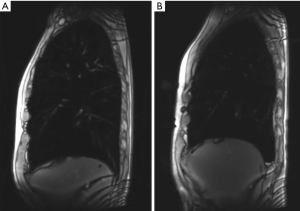

Dynamic MRI

Beside the visualisation of morphologic changes as well as ventilation and time resolved lung perfusion, MRI is a well-recognized technique for the evaluation of lung volumes and respiratory mechanics: Apart from upper-lobe predominance of lung emphysema and heterogeneity, MRI is able to capture impaired motion of the respiratory muscles inclusive the diaphragm, which are additional factors in chronic obstructive pulmonary disease. This is possible, because MRI is an imaging technique, which does not expose the patient to radiation, and image acquisitions can therefore be performed over a longer time. This gives the possibility to evaluate not only static images, but to investigate also for the dynamic and the function of respiration and respiratory muscles. Suga et al. (67) could demonstrate that with dynamic MRI it is possible to non-invasively visualize dynamic respiratory motions of the respiratory muscles. Martini et al. could further show, that the evaluation of breathing dynamic might be beneficial in treatment planning and selection of patients who might benefit the most from LVR (Figure 6) (68).